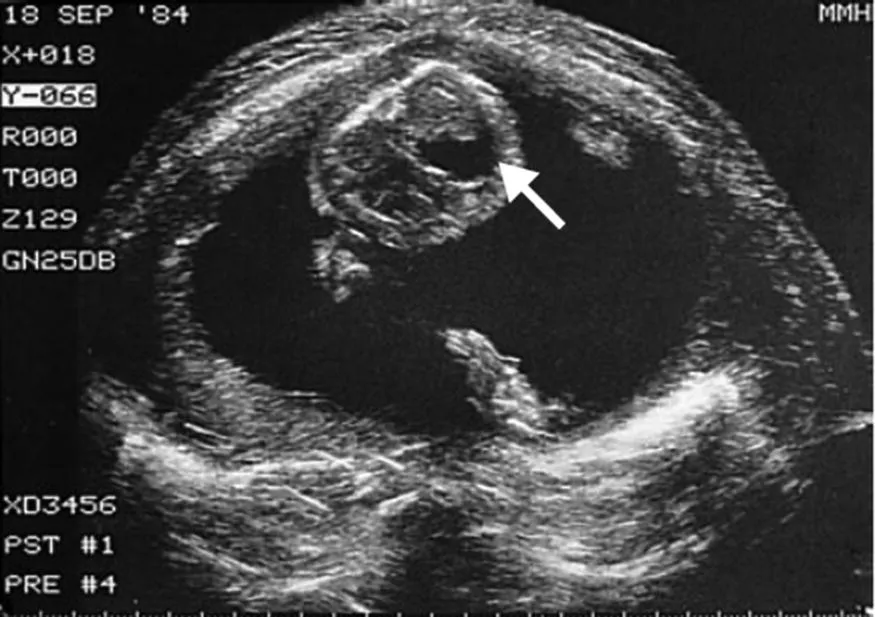

Antenatal Diagnosis: Surgical Aspects

Indications and timing for antenatal ultrasound

Natural history of fetal anomalies

Management following antenatal diagnosis